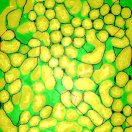

For visual evaluation we provide the segmentation results of the proposed method using two different datasets: and , sampled at different depths within the volumes. The first row shows original microscopy images , , and from and the second row displays the segmentation results corresponding to the first row. To better visualize the segmentation results, we highlighted individual tubules with different colors and overlaid them onto the original microscopy images. Similarly, the third row exhibits original microscopy images , , and from . Their corresponding segmentation results are shown in the fourth row. Note that the model which was trained on was used for during the inference stage. Although the shape, size, and orientation of tubular structures presented in are all different from , the proposed method can still successfully segment and identify individual tubules presented in as well as individual tubules in .